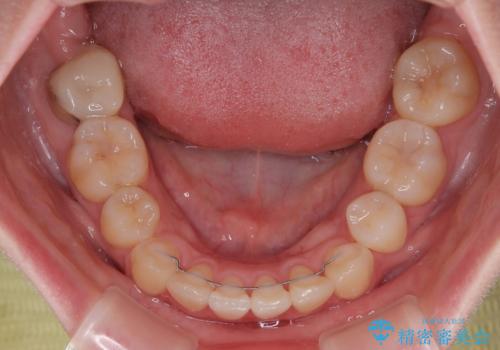

上下の八重歯とクロスバイト ワイヤー装置での抜歯矯正

- 八重歯とクロスバイトを気にして来院された患者様です。

上下ともに八重歯が顕著であり、前歯のクロスバイトがあったため、上下左右の第一小臼歯4本を抜歯し、ワイヤー装置での抜歯矯正を行うこととしました。

20歳ということもあり、歯の移動速度が非常に速く、1年強という短期間であっという間に治療を終えることができました。